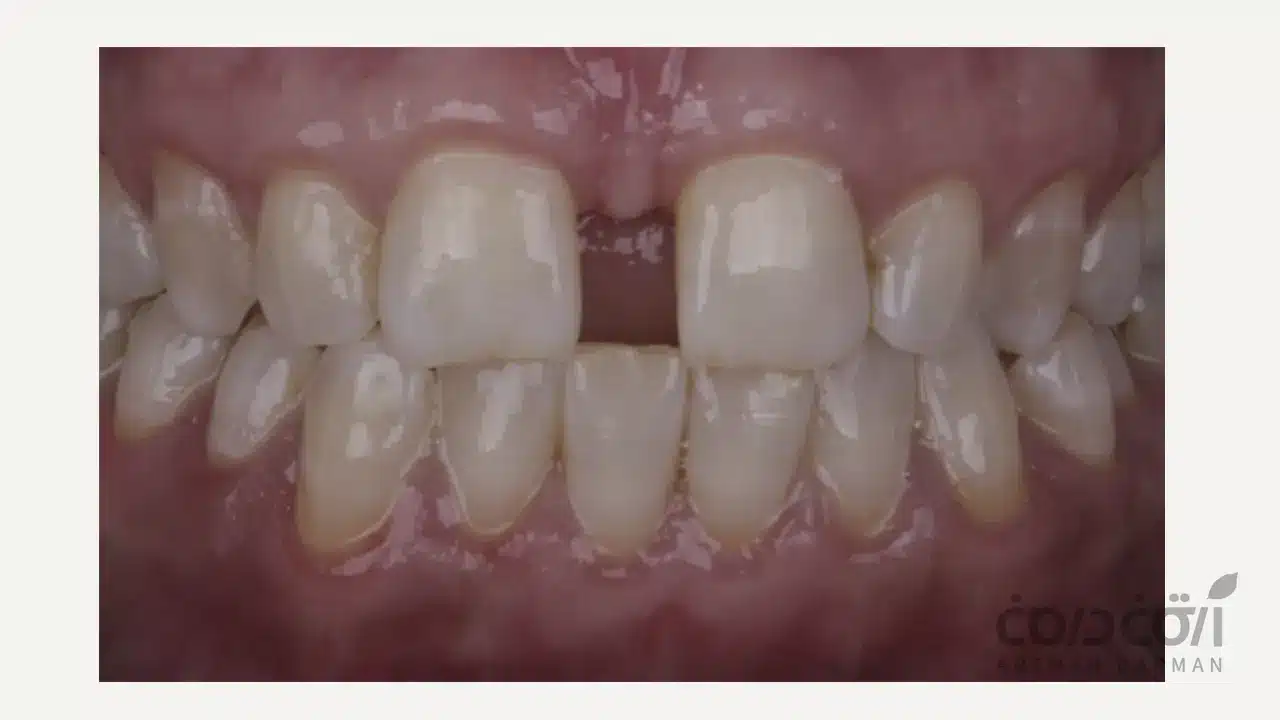

فاصله بین دندان ها که در اصطلاح دندانپزشکی به آن دیاستما (Diastema)گفته می شود، یکی از مشکلات رایج در طرح لبخند است. این وضعیت می تواند هم جنبه زیبایی داشته باشد و هم باعث بروز اختلالات عملکردی شود. دیاستما معمولاً بین دندان های قدامی دیده میشود اما ممکن است در هر ناحیهای از دهان ایجاد شود. خوشبختانه روش های متنوع و مؤثری برای بستن فاصله بین دندان ها وجود دارد که بر اساس نوع و شدت مشکل، توسط دندانپزشک انتخاب می شوند.